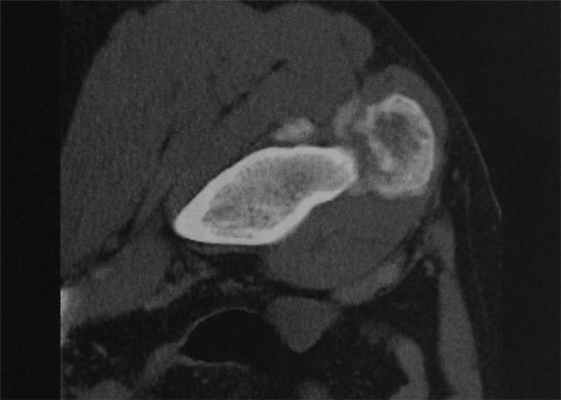

Мужчина 32 лет. КТ. Травматическое повреждение правой паховой области за несколько лет до исследования. В месте прикрепления прямой мышцы живота округлый зрелый участок окостенения с периферическим формированием нового кортикального слоя, типичный для оссифицирующего миозита. В отличие от околокостной остеосаркомы, при оссифицирующем миозите кальцинаты крупнее на периферии, чем в центре.

Что покажут снимки КТ костей конечностей при оссифицирующем миозите

- Зональная структура (кальцинированная периферическая зона с некальцинированным центром) определяется лучше, чем при рентгенологическом исследовании

- Лучше визуализируется расстояние от кортикального слоя расположенной рядом кости.